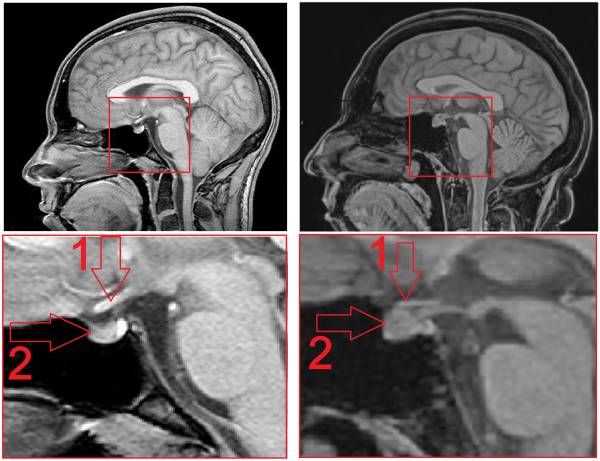

Разрастание опухоли вне участка расположения гипофиза, особенно вертикальный ее рост, может повреждать гипоталамическую структуру. Благодаря новым технологиям диагностики, таким как МРТ, стала возможна ранняя диагностика микроаденомы. Человек, чувствуя в организме те или иные отклонения, может обратиться к врачу и чаще всего специалист направляет его на МРТ. Своевременная диагностика позволяет предотвратить дальнейшее развитие болезни и возникшие осложнения чаще всего консервативным путем.

- Магнитно-резонансная томография (МРТ) и компьютерная томография (КТ). Самый эффективный метод диагностики, который дает полную картину о болезни и каких-либо изменениях в гипофизе, ее структуре. Диффузно-неоднородная структура гипофиза говорит о наличии заболевания.